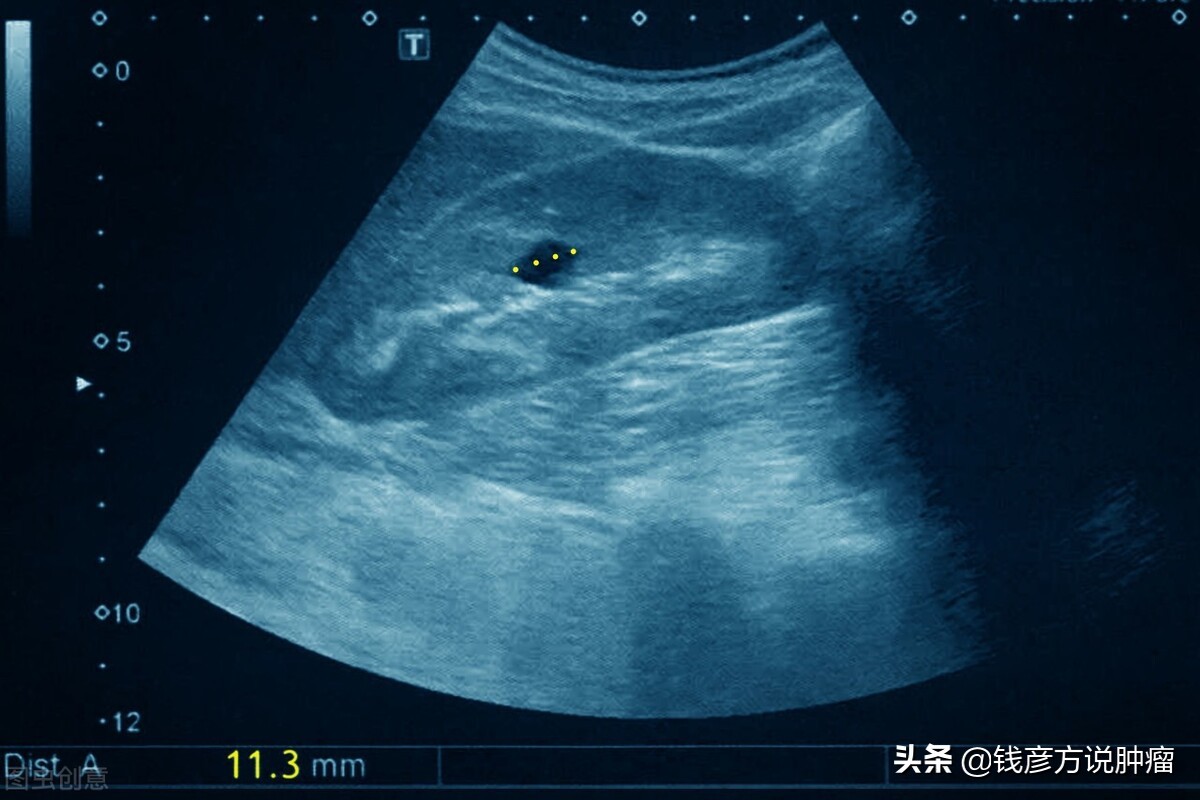

肾囊肿有的是单发的,在肾里面是个单发囊肿,有的是多发囊肿,还有多囊肾,有的单发囊肿很大,这样的情况怎么办?

一方面这个囊肿如果大的话,就要穿刺,也就是说把针头穿到囊肿里面。

囊肿它是一种囊液,临床有一种方法把它抽出来,用无水酒精的方法粘住它,以后就不会再长了。

我记得在前年有一个病例,他当时囊肿五点几,后来变成三点几,也就说囊肿变小的话,就可以减少对输尿管的压迫引起肾水肿的结果,所以说囊肿是可以治疗的。